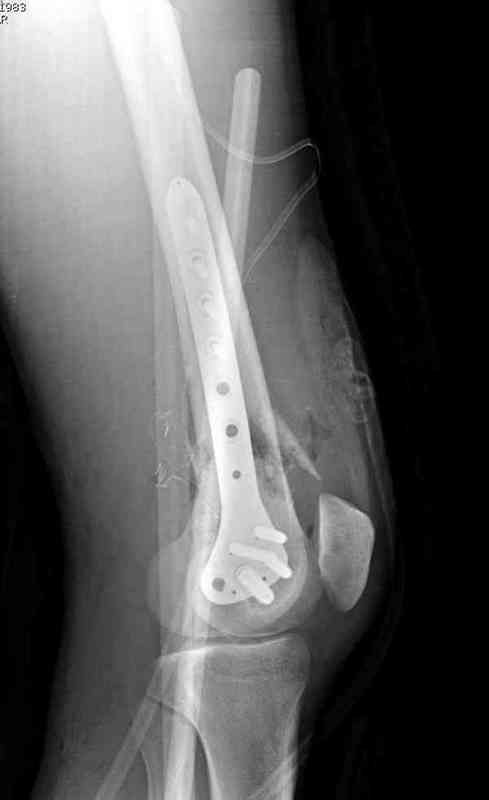

Больная К. с тугим ложным суставом н/3 бедра. Травма в 2005 г.-закрытый перелом, остеосинтез в аппарате Илизарова. В 2006 г. оперирована по поводу несросшегося перелома.

В ноябре 2006 г. демонтаж аппарата, после чего в течении месяца развилась вальгусная деформация. Имеется патологическая подвижность. Объем движений в коленном суставе 180-140. На обсуждение выносятся варианты лечения погружными конструкциями.

The patient with non-union of the distal femur. Trauma in 2005 - closed fracture of the femur, external fixation with Ilizarov apparatus. Non-union. In 2006 open reduction and external fixation with Ilizarov apparatus. In November 2006 the apparatus was removed, after that valgus deformation developed. There is pathological mobility. The knee motion 180-140. We'd like to discuss options of internal fixation.